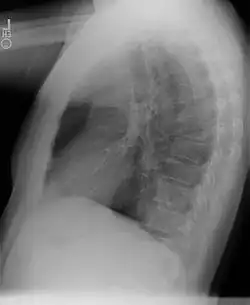

Wada przebiegająca bezobjawowo, bez połączenia z oskrzelem, może być wykryta przypadkowo na zdjęciu przeglądowym klatki piersiowej jako okrągława masa o wysyceniu typowym dla tkanek miękkich, najczęściej zlokalizowana nad przeponą w dolno-tylnej części lewego płuca. Obraz radiologiczny objawowej sekwestracji płucnej naśladuje zmiany torbielowate, jamiste lub marskie. Aortografia pozwala ocenić zaopatrzenie zmiany w naczynia tętnicze.